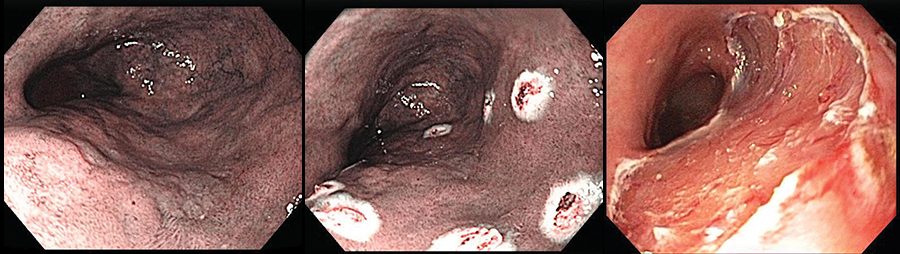

Reparación de desajuste de ADN deficiente en cáncer rectal

Un estudio ofrece un punto de partida para las pruebas de inmunoterapia en cáncer rectal